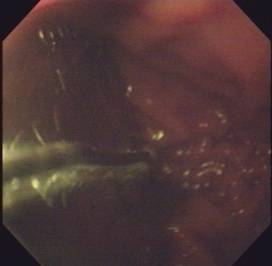

3.内镜和细胞学检查对本病的诊断帮助不大,但可用于本病与食管贲门癌等病之间的鉴别诊断。